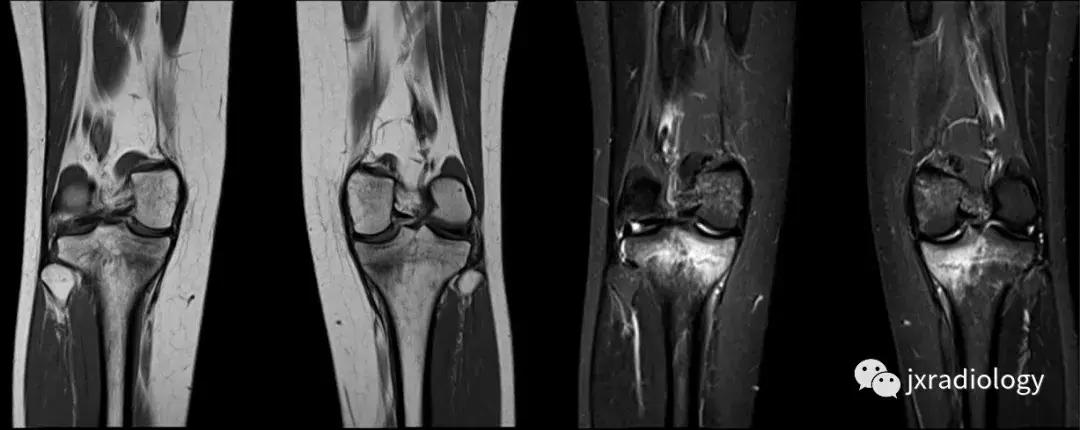

图3:应力(疲劳)骨折:女,25岁,最近在没有适当热身的情况下在健身房参与剧烈运动的冠状位T1WI和STIR图像。她主诉出现双侧内侧胫骨疼痛。在双侧胫骨中,内侧近端应力性骨折是明显的。

图4:SIF(软骨下不全性骨折):在过去,每当在股骨内侧髁上观察到这种软骨下病变时,它就被标记为膝关节自发性骨坏死(SONK)。现在它被认为是一个不全性骨折。这些不全性骨折通常发生在股骨内侧髁和股骨头,并存在于老年人中(它们与骨质疏松症和生物力学改变相关,如在不稳定的半月板损伤中。与其他应力性骨折类似,低信号的骨折线在水敏性序列(a,b:冠状和矢状PDWI-FS)上被高信号的骨髓水肿包围。